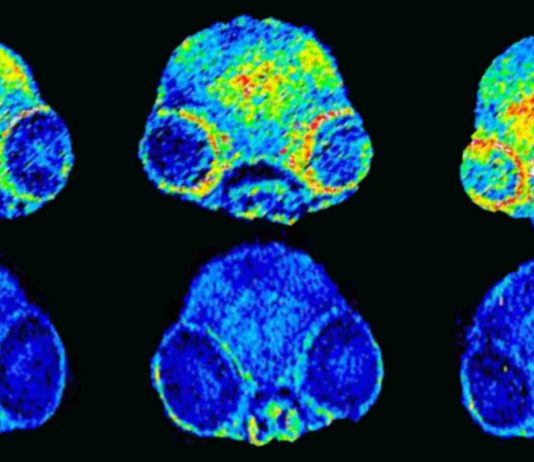

For this proof-of-principle study, researchers at the UCL Great Ormond Street Institute for Child Health (GOS ICH) and the UCL Cancer Institute modified the...